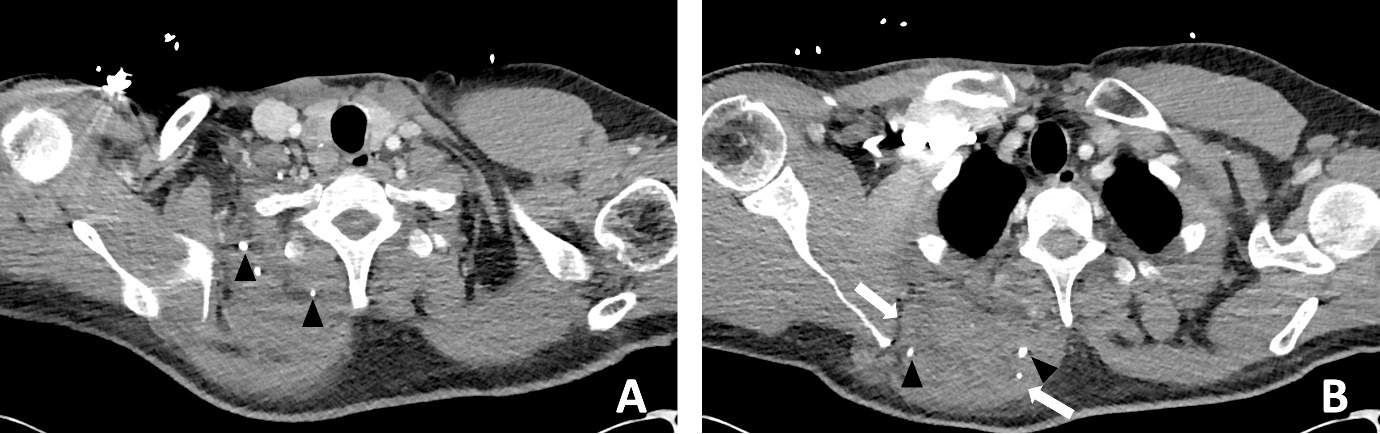

Blood results revealed a high white blood cell count (30.3 × 109/L) with neutrophilia and high C-reactive protein (245.2 mg/L). An X-ray of the hip was performed and interpreted as normal, although in retrospect, phleboliths were present in the region of the adductor muscles (Figure 1). Abdominal CT was normal. Fat stranding, soft tissue swelling and possible fluid collections were identified within the anterior and medial thigh on CT. Retrospectively, there were also multiple intramuscular phleboliths within the adductor muscles (Figure 2).

In retrospect, the presence of intramuscular phleboliths on CT in the cases presented above was the best clue to the diagnosis of an infected VM. Phleboliths occur in approximately 30 per cent of VMs.15 Intramuscular phleboliths have a limited imaging differential diagnosis and are generally taken to be pathognomic of VM.16 Radiologist and clinician awareness of this rare presentation of VMs is important; if intramuscular phleboliths are identified, the diagnosis of VM should be raised and the use of MRI may further assist in the diagnosis. If clinical doubt remains in an acutely unwell patient, prompt surgery to exclude necrotising soft tissue infection is prudent.

Timely surgical exploration is indicated in septic patients where necrotising soft tissue infection cannot be excluded. However, it is important to consider rare conditions that may present similarly, such as infected VMs. The presence of intramuscular phleboliths on CT, especially in a child, is the best imaging clue to this unusual diagnosis and should not be overlooked.